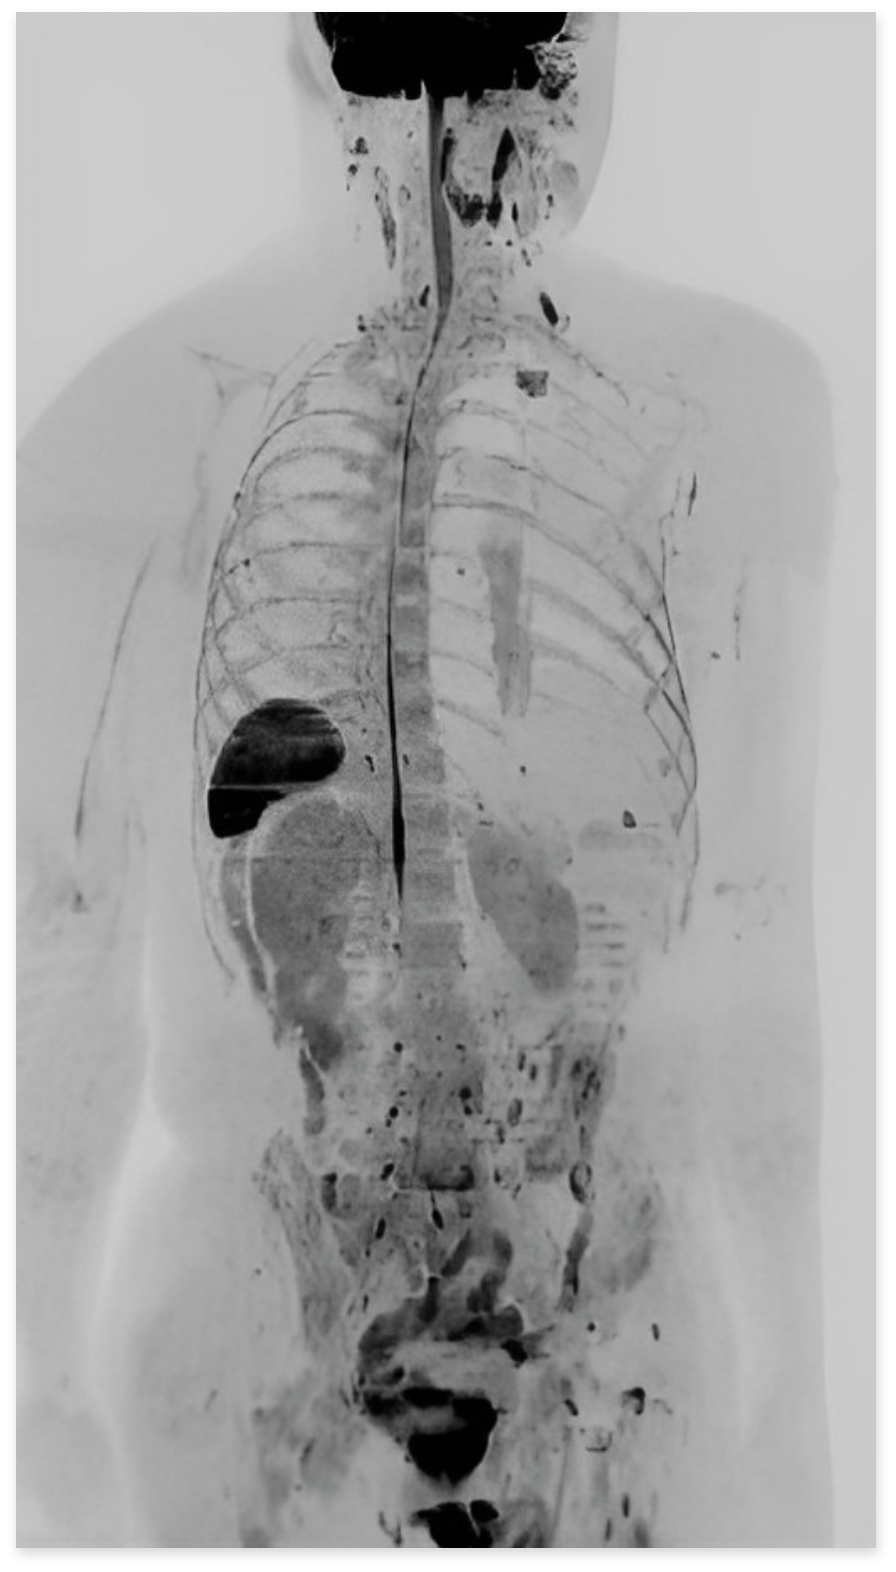

ドゥイブス(DWIBS) 検査とは?

MRI技術の進化によって実現した、全身のがん検査です。従来のPET-CTがエネルギー代謝に着目して悪性腫瘍を探すのに対し、ドゥイブス法は、 細胞密度の高さに着目し、細胞間の水の動きから悪性腫瘍を発見します。これにより、体への負担が少なく、短時間で正確な検査が可能です。

放射線被曝ゼロで体に優しい検査

従来のPET-CTと異なり、ドゥイブス法では放射線被曝が一切ありません。放射線の影響を心配することなく、安心して全身の健康状態をチェックできます。

短時間で完了する全身チェック

ドゥイブス法による全身検査は、わずか約30分で完了。全身を効率的にチェックでき、忙しい方でも負担をかけずにご利用いただけます。

痛みや不快感がない快適な検査

注射や造影剤を使用しないため、痛みや不快感がほとんどありません。特に乳がん検査では、圧迫や痛みがなく、服を着たまま安心して受けていただけます。

ドゥイブス法とPET-CTの比較

ドゥイブス法は、短時間で全身のがんや他の疾患を検出できるだけでなく、

放射線による被曝がないため、体への負担が非常に少ない検査法です。

特に、糖尿病患者でも問題なく受けられる点や、痛みのない検査法として多くの方に選ばれています。

他の検査法と比較しても、安全性と利便性の高さが際立っています。